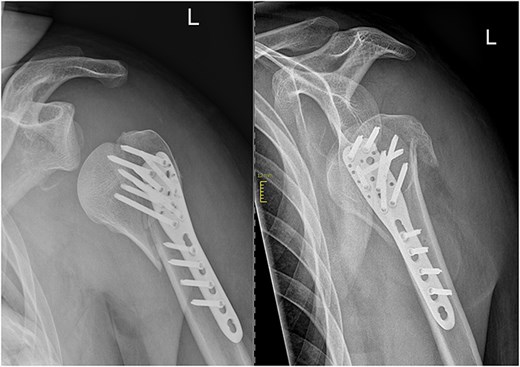

In subsequent clinical and radiological follow-ups at 2, 6, and 24 weeks postoperative, the humeral head depression showed regression, and the patient was able to progressively increase joint demands (Fig. 3). Training under physiotherapeutic supervision was difficult because of his secondary diagnoses. In the end after 6 Months he was unaffected in his daily living and painless.